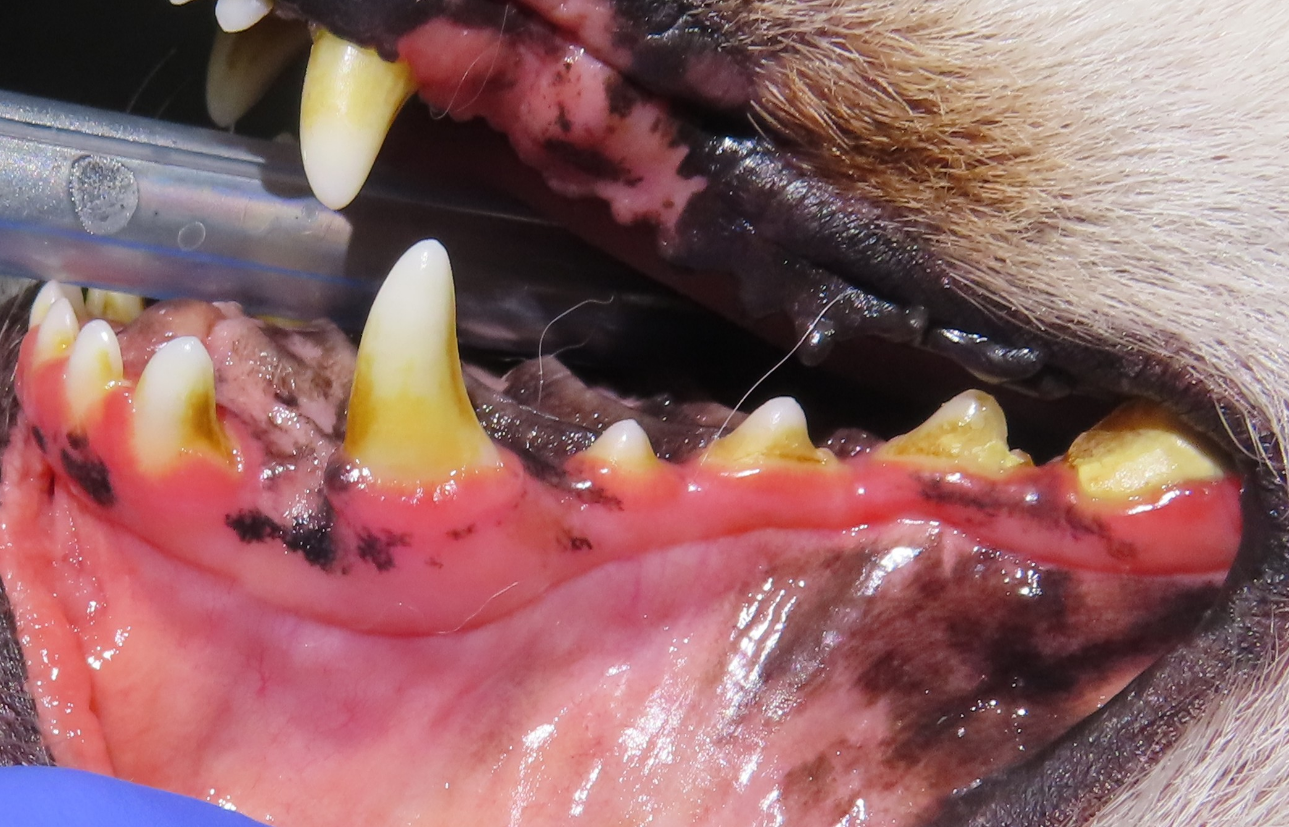

이번 사례의 아이 역시 송곳니 뒤쪽 어금니 부위에 치은퇴축이 관찰되었고, 치아 표면 일부에 미세한 파절이 확인되었습니다. 겉으로 보기에는 발치를 고려해야 할 것처럼 보일 수 있는 상태였습니다.

그러나 구강 질환의 결정은 외형만으로 판단하지 않습니다. 실제로 중요한 것은 치아를 지탱하는 내부 구조가 얼마나 유지되고 있는지입니다. 이를 확인하기 위해 발치 여부를 가르는 정밀 검사를 진행하였습니다.

3. 치주낭 깊이 측정

탐침을 이용해 잇몸과 치아 사이의 치주낭 깊이를 측정합니다. 염증이 심해지면 이 공간이 깊어지고 세균이 뿌리 쪽으로 침투하게 됩니다.

이번 사례에서는 염증 반응은 있었지만 치주낭 깊이는 관리 가능한 수준으로 확인되었습니다.